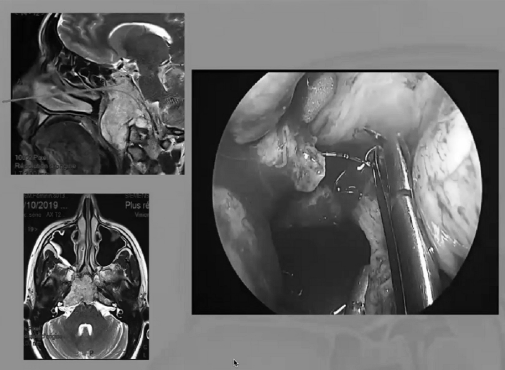

▼下圖所示案例腫瘤看著很大,然后用30度、45度甚至70度的內(nèi)鏡,我們有很多帶角度的器械,利用這些器械就可以切除腫瘤??梢韵惹虚_黏膜,然后把蝶竇內(nèi)的黏膜推開,然后進(jìn)入腫瘤。目前我們正在努力的開發(fā)這方面的器械,沒(méi)有這些器械我們是做不了手術(shù)的。

手術(shù)圖片

▼下面就是我所說(shuō)的有角度的器械,然后我們用脂肪來(lái)修補(bǔ),我們?cè)趦?nèi)鏡下做縫合,在內(nèi)鏡下做縫合很復(fù)雜難度很大,所以很花時(shí)間,但是它是值得的。

內(nèi)鏡手術(shù)圖片

內(nèi)鏡手術(shù)圖片1

▼這是術(shù)后的MRI,大家看到的高信號(hào)的是脂肪組織,我覺(jué)得利用內(nèi)鏡到達(dá)顱頸交界區(qū)更簡(jiǎn)單。

術(shù)后的MRI圖片